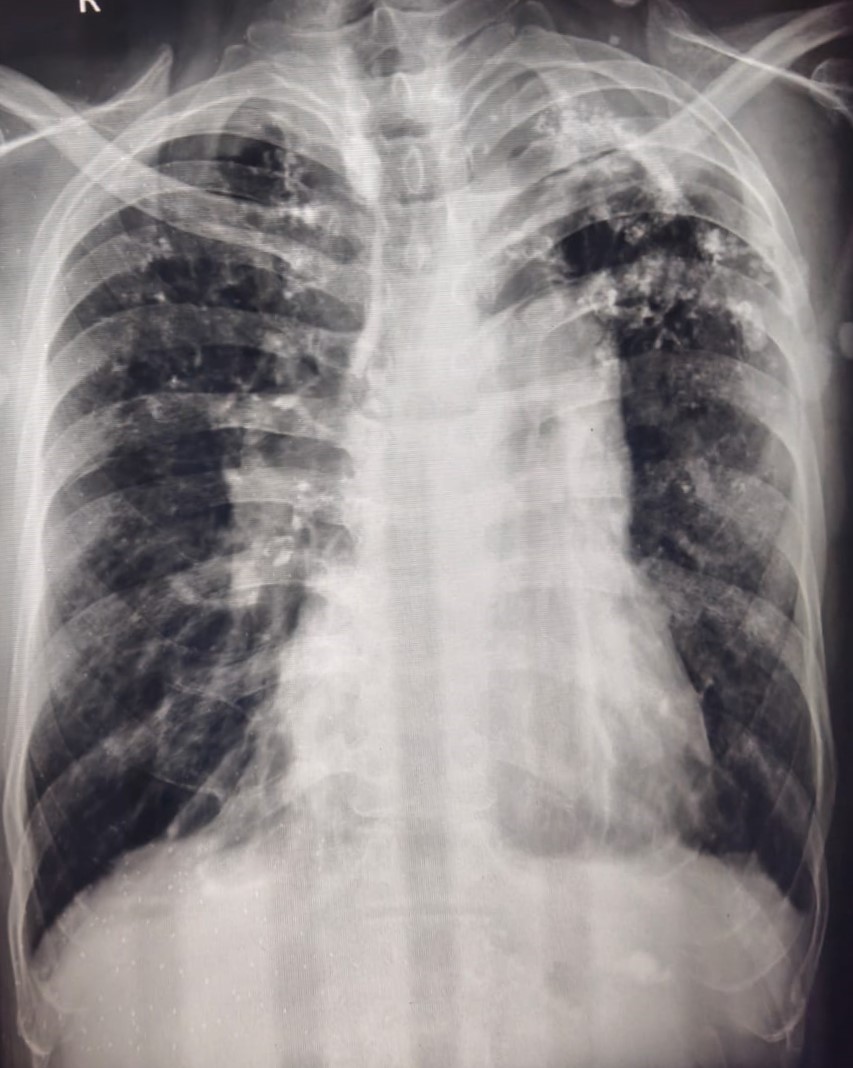

| 318 | IGGMC, Nagpur, Nagpur | P2 | 29-4154 | Tahera Bee | Consent taken on Paper | 70 Yrs. |

Provisional Diag : Post TB Bilateral Bronchiectasis

Final Diag : Post TB sequalae, Bilateral Bronchiectasis In Lower Lobe With Type 1 Respi Failure With Sepsis With Septic Shock With SYST HTN |

Post TB Sequelae | Abnormality visible on x-ray |